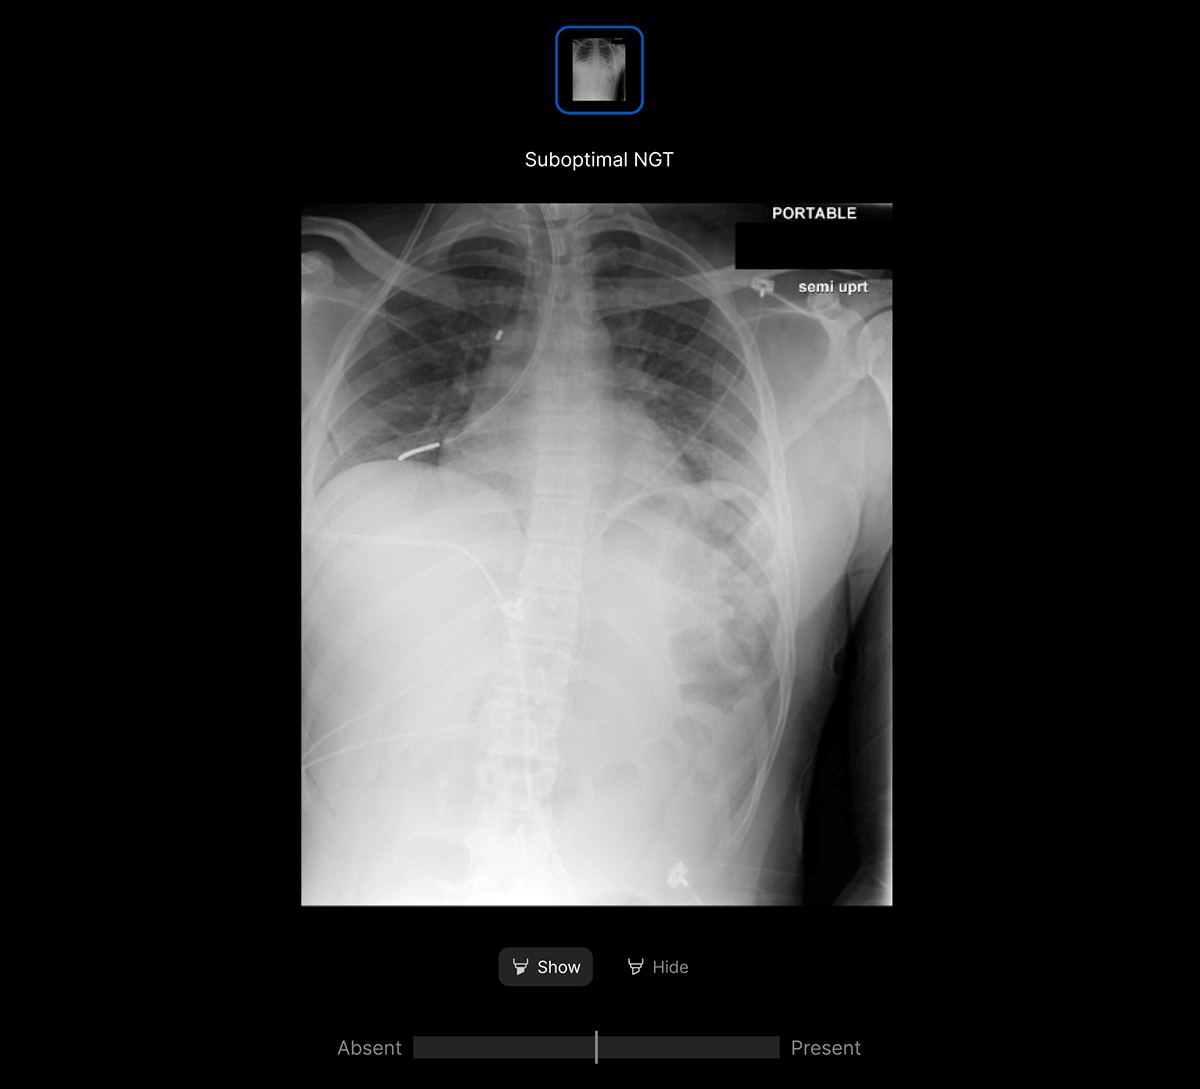

The user-interface integrates seamlessly with PACS/ RIS, displaying a resizable, no-click overlay window with findings and localisation.

- Explainable AI features such as localisation and a confidence bar to improve AI interpretability and clinical decision making.

- Fully integrated into the existing clinical workflow, with a user-friendly, ‘no click’ Viewer.